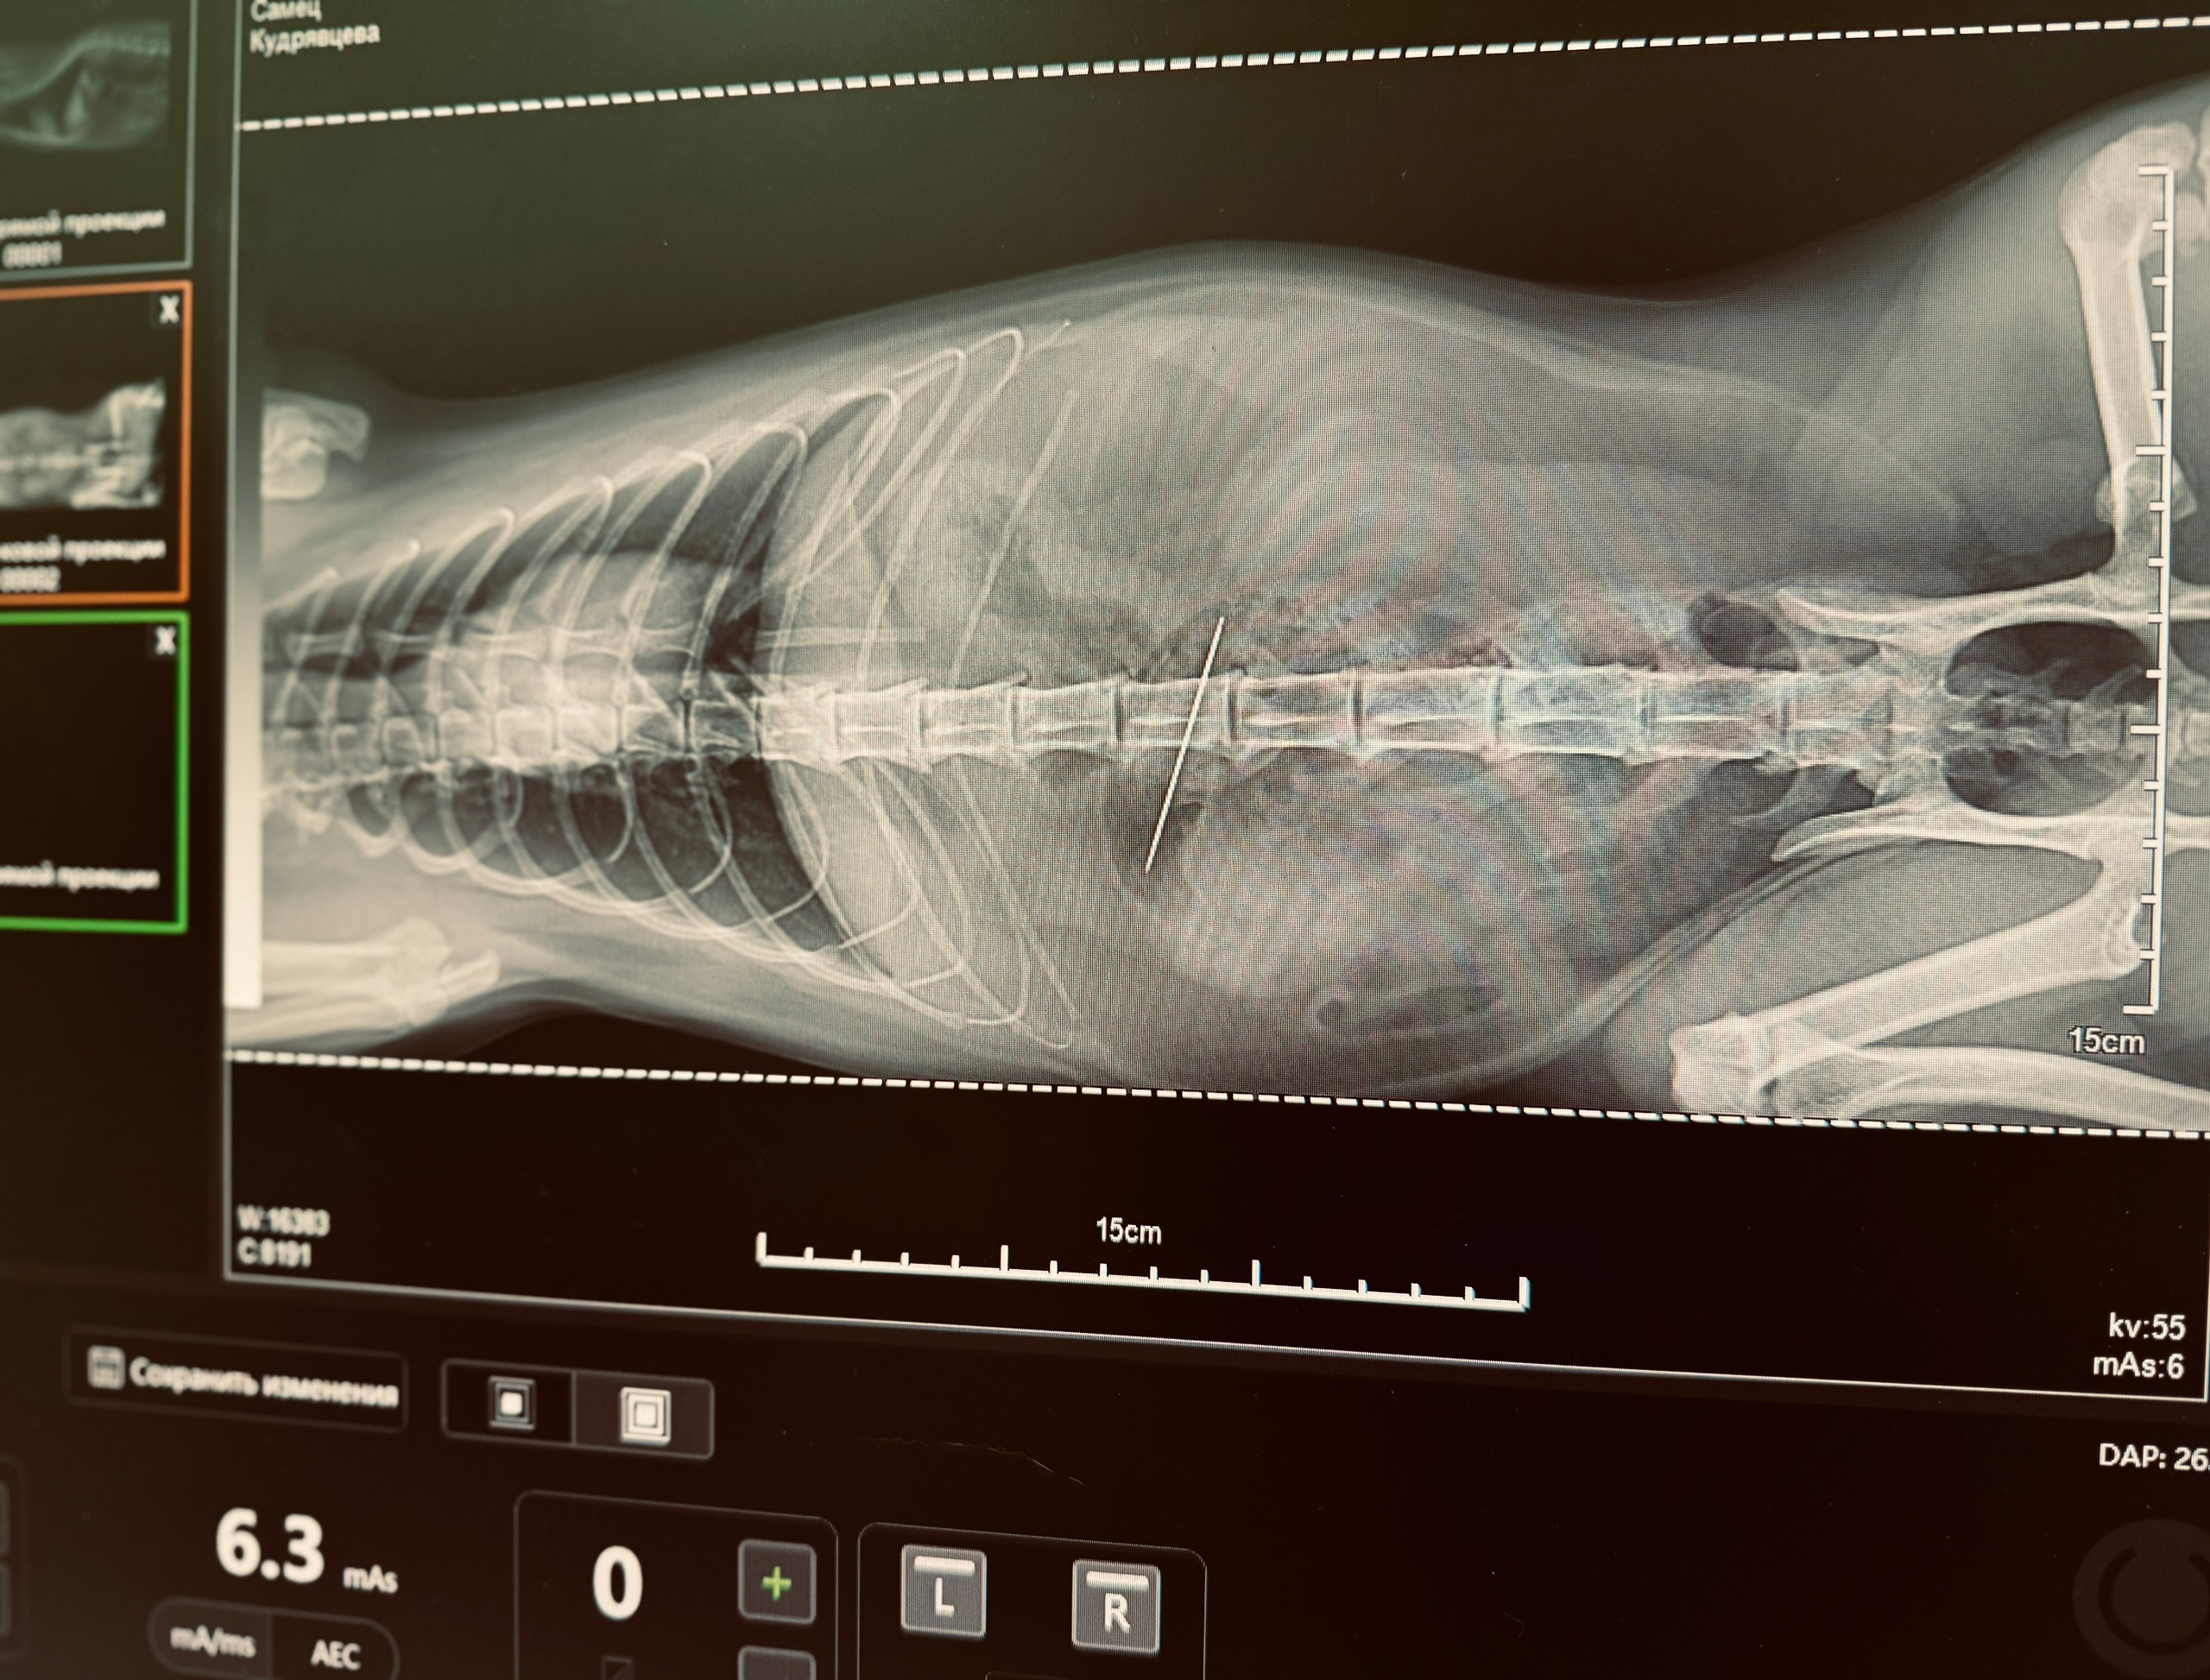

Именно в такую историю попала кошка Фрося. Играя с ниткой, она случайно проглотила иглу. Итог – экстренная операция. Сейчас Фрося восстанавливается.